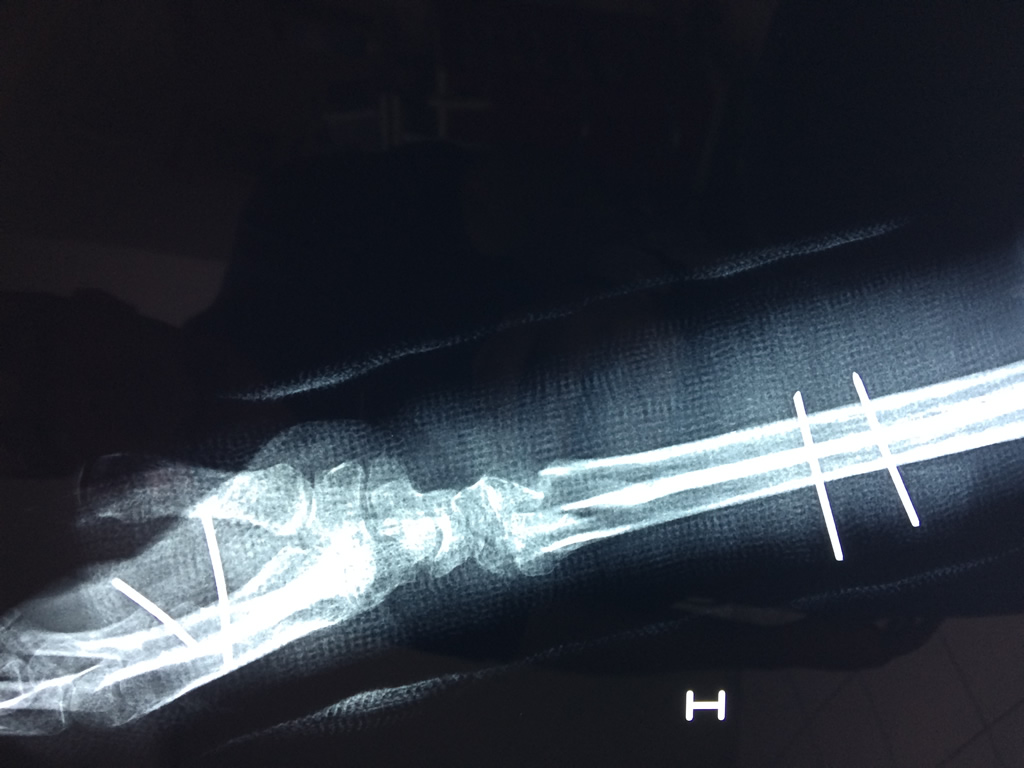

Cirugía de Muñeca y Mano

Los procedimientos más comunes en cirugía de la mano son aquellos destinados a reparar traumatismos, incluyendo lesiones de tendones, nervios, vasos sanguíneos, y articulaciones; huesos fracturados; y quemaduras, cortes, y otros daños de la piel.